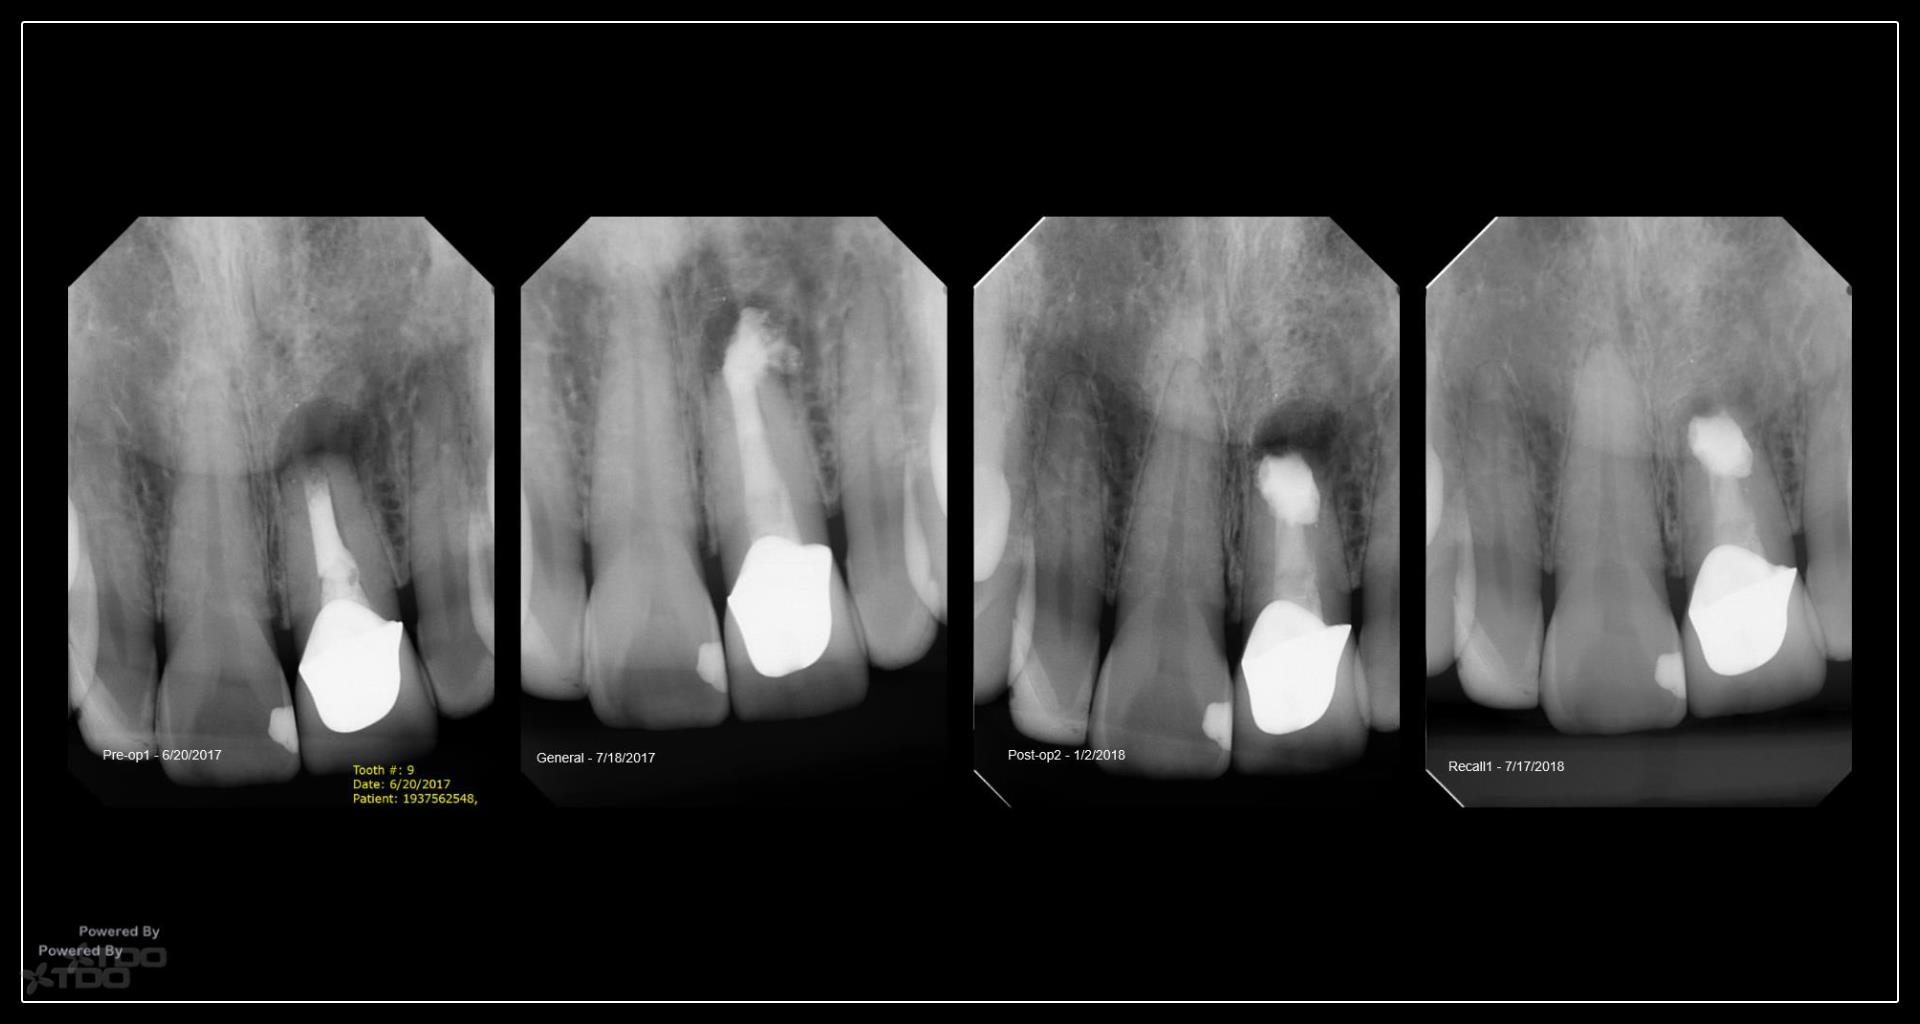

This was interesting because a root frac ture was seen where the prior apico was done. The MTAS was removed and Brassler putty used in this case. Will take a 1 yr CBCT and we will know more. Don’t usually get so much scar formation–so this was surprising…..